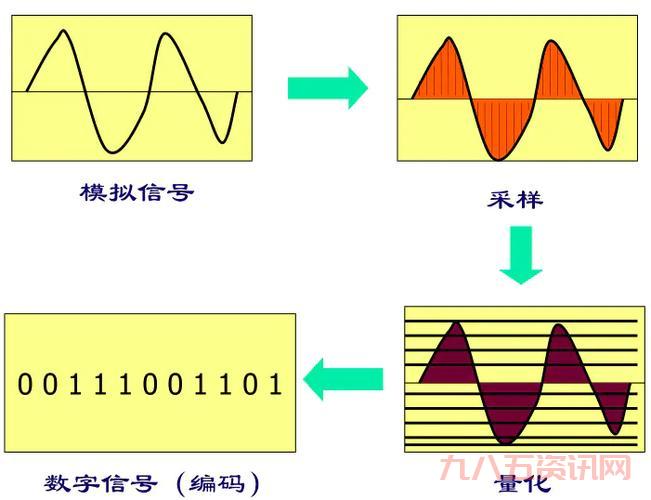

那天,我照常在家搞我的設備,突然就琢磨起這個“t2”到底是个起初我也不懂,就到處找資料,問人,可算是把“t2”是個啥弄明白。這玩意兒在醫學上還是核磁共振成像裡頭的一個關鍵指標,主要说的就是那個橫向磁化矢量恢復到一個平衡時狀態的時間,大概是這個意思。

然後我繼續深入解,發現這“t2”還分好幾種情況。

- 像那個頸椎T2,說的就是在做核磁共振的時候,那個橫向磁化矢量衰減到最大值的百分之37所需要的時間。

- 還有那個T2信號影,就是說在核磁共振成像裡頭,組織在T2加權圖像上的表現。

我先是試各種參數,什麼調整那個掃描時間,改變信號強度,可是弄來弄去都沒啥效果。後來,我想著是不是得換個思路,既然“t2”跟水有關,那我是不是可以在這上面做做文章?

於是,我就開始嘗試在樣品裡加水,減水,把不同的東西放進去試試看,觀察信號的變化。你別說,這方法還真管用!當我調整樣品裡的水含量時,那個信號就開始跟著變,有時候變亮,有時候變暗,看著真是有點意思!

就這樣,我反覆試驗,記錄數據,總算是摸清這個“偽t2”的門道。原來,通過改變樣品裡水的含量,就能模擬出類似T2信號的變化,這不就是“偽t2”嘛